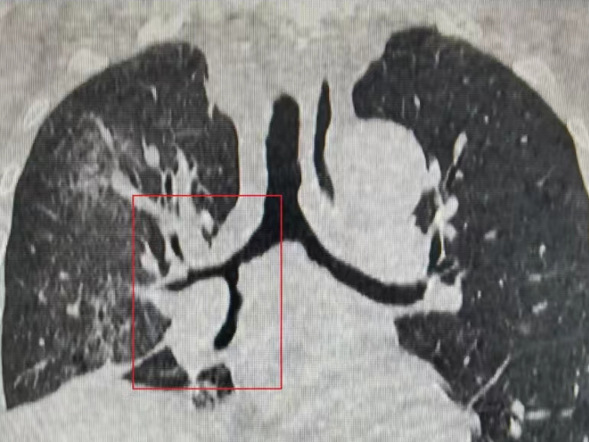

家住外县的张先生今年68岁,来我院就诊之前,出现呼吸困难和胸痛等症状,血氧饱和度很低。在当地医院做了一个胸部CT检查,检查结果显示患者右主支气管里有个肿物,但堵塞程度不是很明显。随后,患者又去其他医院再次做了一个胸部CT检查,相比于之前检查结果,患者右侧主支气管肿物要比之前增大一些,便辗转来到我院接受治疗。患者来到医院后,身体状况非常差,胸部CT检查显示,患者右侧主支气管完全被肿物所填塞,属于急性快速进展气道梗阻,病情危重。对此,我院呼吸与危重症医学科一病区医护团队迅速提供急救方案,快速缓解患者梗阻症状。据我院呼吸与危重症医学科一病区副主任牟海军介绍,患者前来就诊时情况紧急,需立即进行呼吸介入治疗,于是当时对其采用了冷冻、圈套、电刀的治疗。经过治疗后,患者呼吸困难的症状明显缓解,胸部CT复查以及镜下影像显示,患者气道狭窄被完全解除,为后续患者进一步治疗赢得了宝贵的时间。

术前胸部CT显示气管下段部狭窄,右侧主支气管完全闭塞,右肺全肺不张

术后第一天复查胸部CT显示气管下段及右侧主支气管狭窄消失,右侧肺不张明显好转